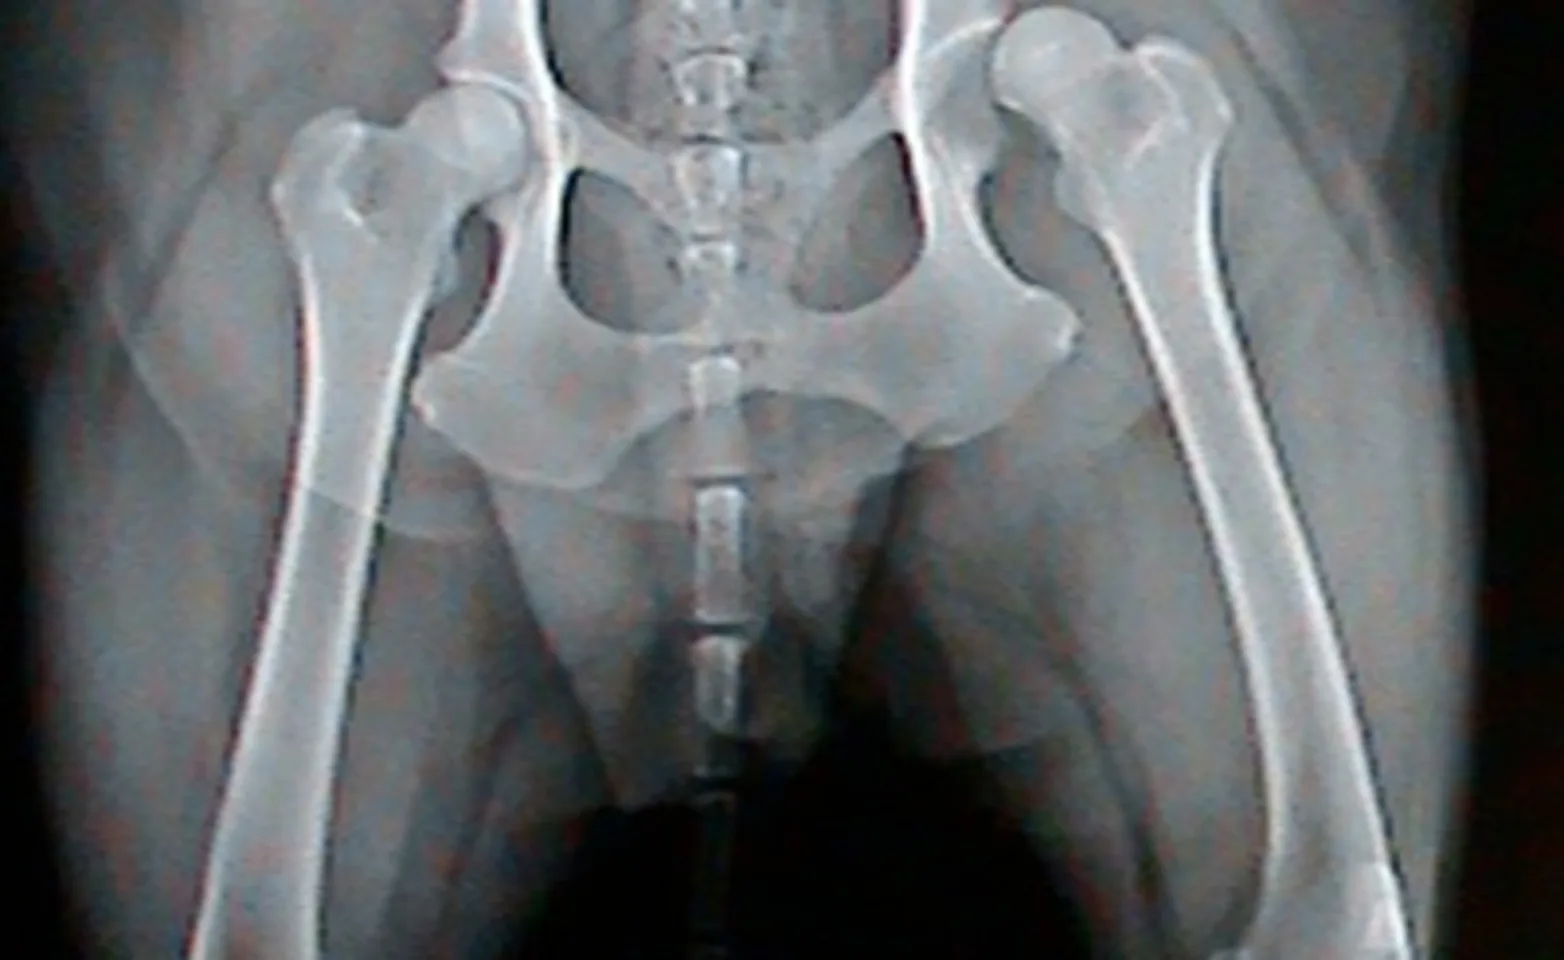

Hip dysplasia is a condition affecting both dogs and cats. With this condition, the hip joint develops abnormally such that the bones within the joint do not form a nice tight fit. The wear and tear that results from hip dysplasia lead to a flattened femoral head (top of the thigh bone that sits in the hip joint) that gradually slips out of a progressively more flattened joint socket. New bone may develop in the area, causing arthritic pain—this and the laxity (looseness) in the joint may lead to lameness and reduced function.

There are basically two categories of hip surgery when it comes to hip dysplasia. These differ in that one involves early surgical intervention as a preventive measure while the other focuses on alleviating the pain and lameness associated with an unstable arthritic hip joint. This involves surgery on immature dogs in an attempt to improve hip stability so as to minimize future arthritis and pain. The second focuses on treatment of a painful arthritic hip joint. Unfortunately the vast majority of hip surgeries are performed on mature dogs that have developed severe arthritis, are painful, and have not responded adequately to medical management since early detection of hip dysplasia can be quite difficult and require specific tests.